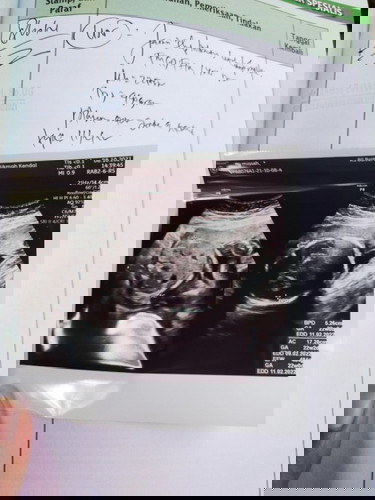

Jeniskelamin ,bund mau tanya kalo USG jenis kelamin usia 5 bulan setengah itu udah akurat blm yaa ?

kalo posisi janin nya bagus pas USG biasanya bisa akurat Bun. kalo msh setengah menutupi kadang dr cuma memprediksi